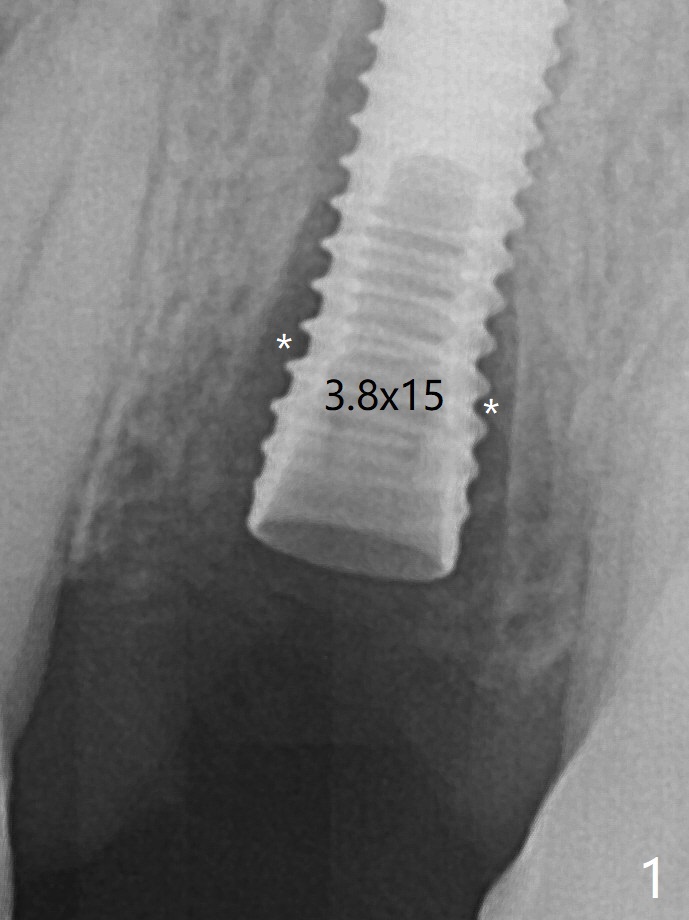

Due to short apical bone (Fig.5,7), a long dummy implant (3.8x15 mm) is placed with periimplant space immediately post extraction (Fig.1 *). The final implant is larger (4.5x15 mm) with simultaneous periimplant bone graft (Fig.2 <,当时骨粉一定用的多,压得紧,好像进入螺纹). The native bone (higher in bone density, Fig.9 white arrowheads, as compared to black one (for bone graft)) appears to have grown into the space between implant threads 5.5 months postop. Sinus Lift Last Next XinWei, DDS, PhD, MS 1st edition 06/21/2019, last revisionn 06/13/2021